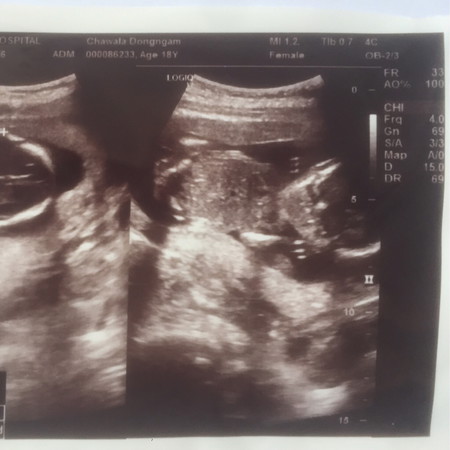

ซาวด์ตอน4เดือนหมอไม่ได้บอกว่าผู้ชายหรือผู้หญิง ให้แม่ๆช่วยดูหน่อยค่ะ ผู้ชายหรือผู้หญิงคะ ตอนนี้38wแล้วยังไม่รู้เพศเลยค่ะ???

ไม่ใช้ตรงหว่างขาน้อง ดูยากคะ